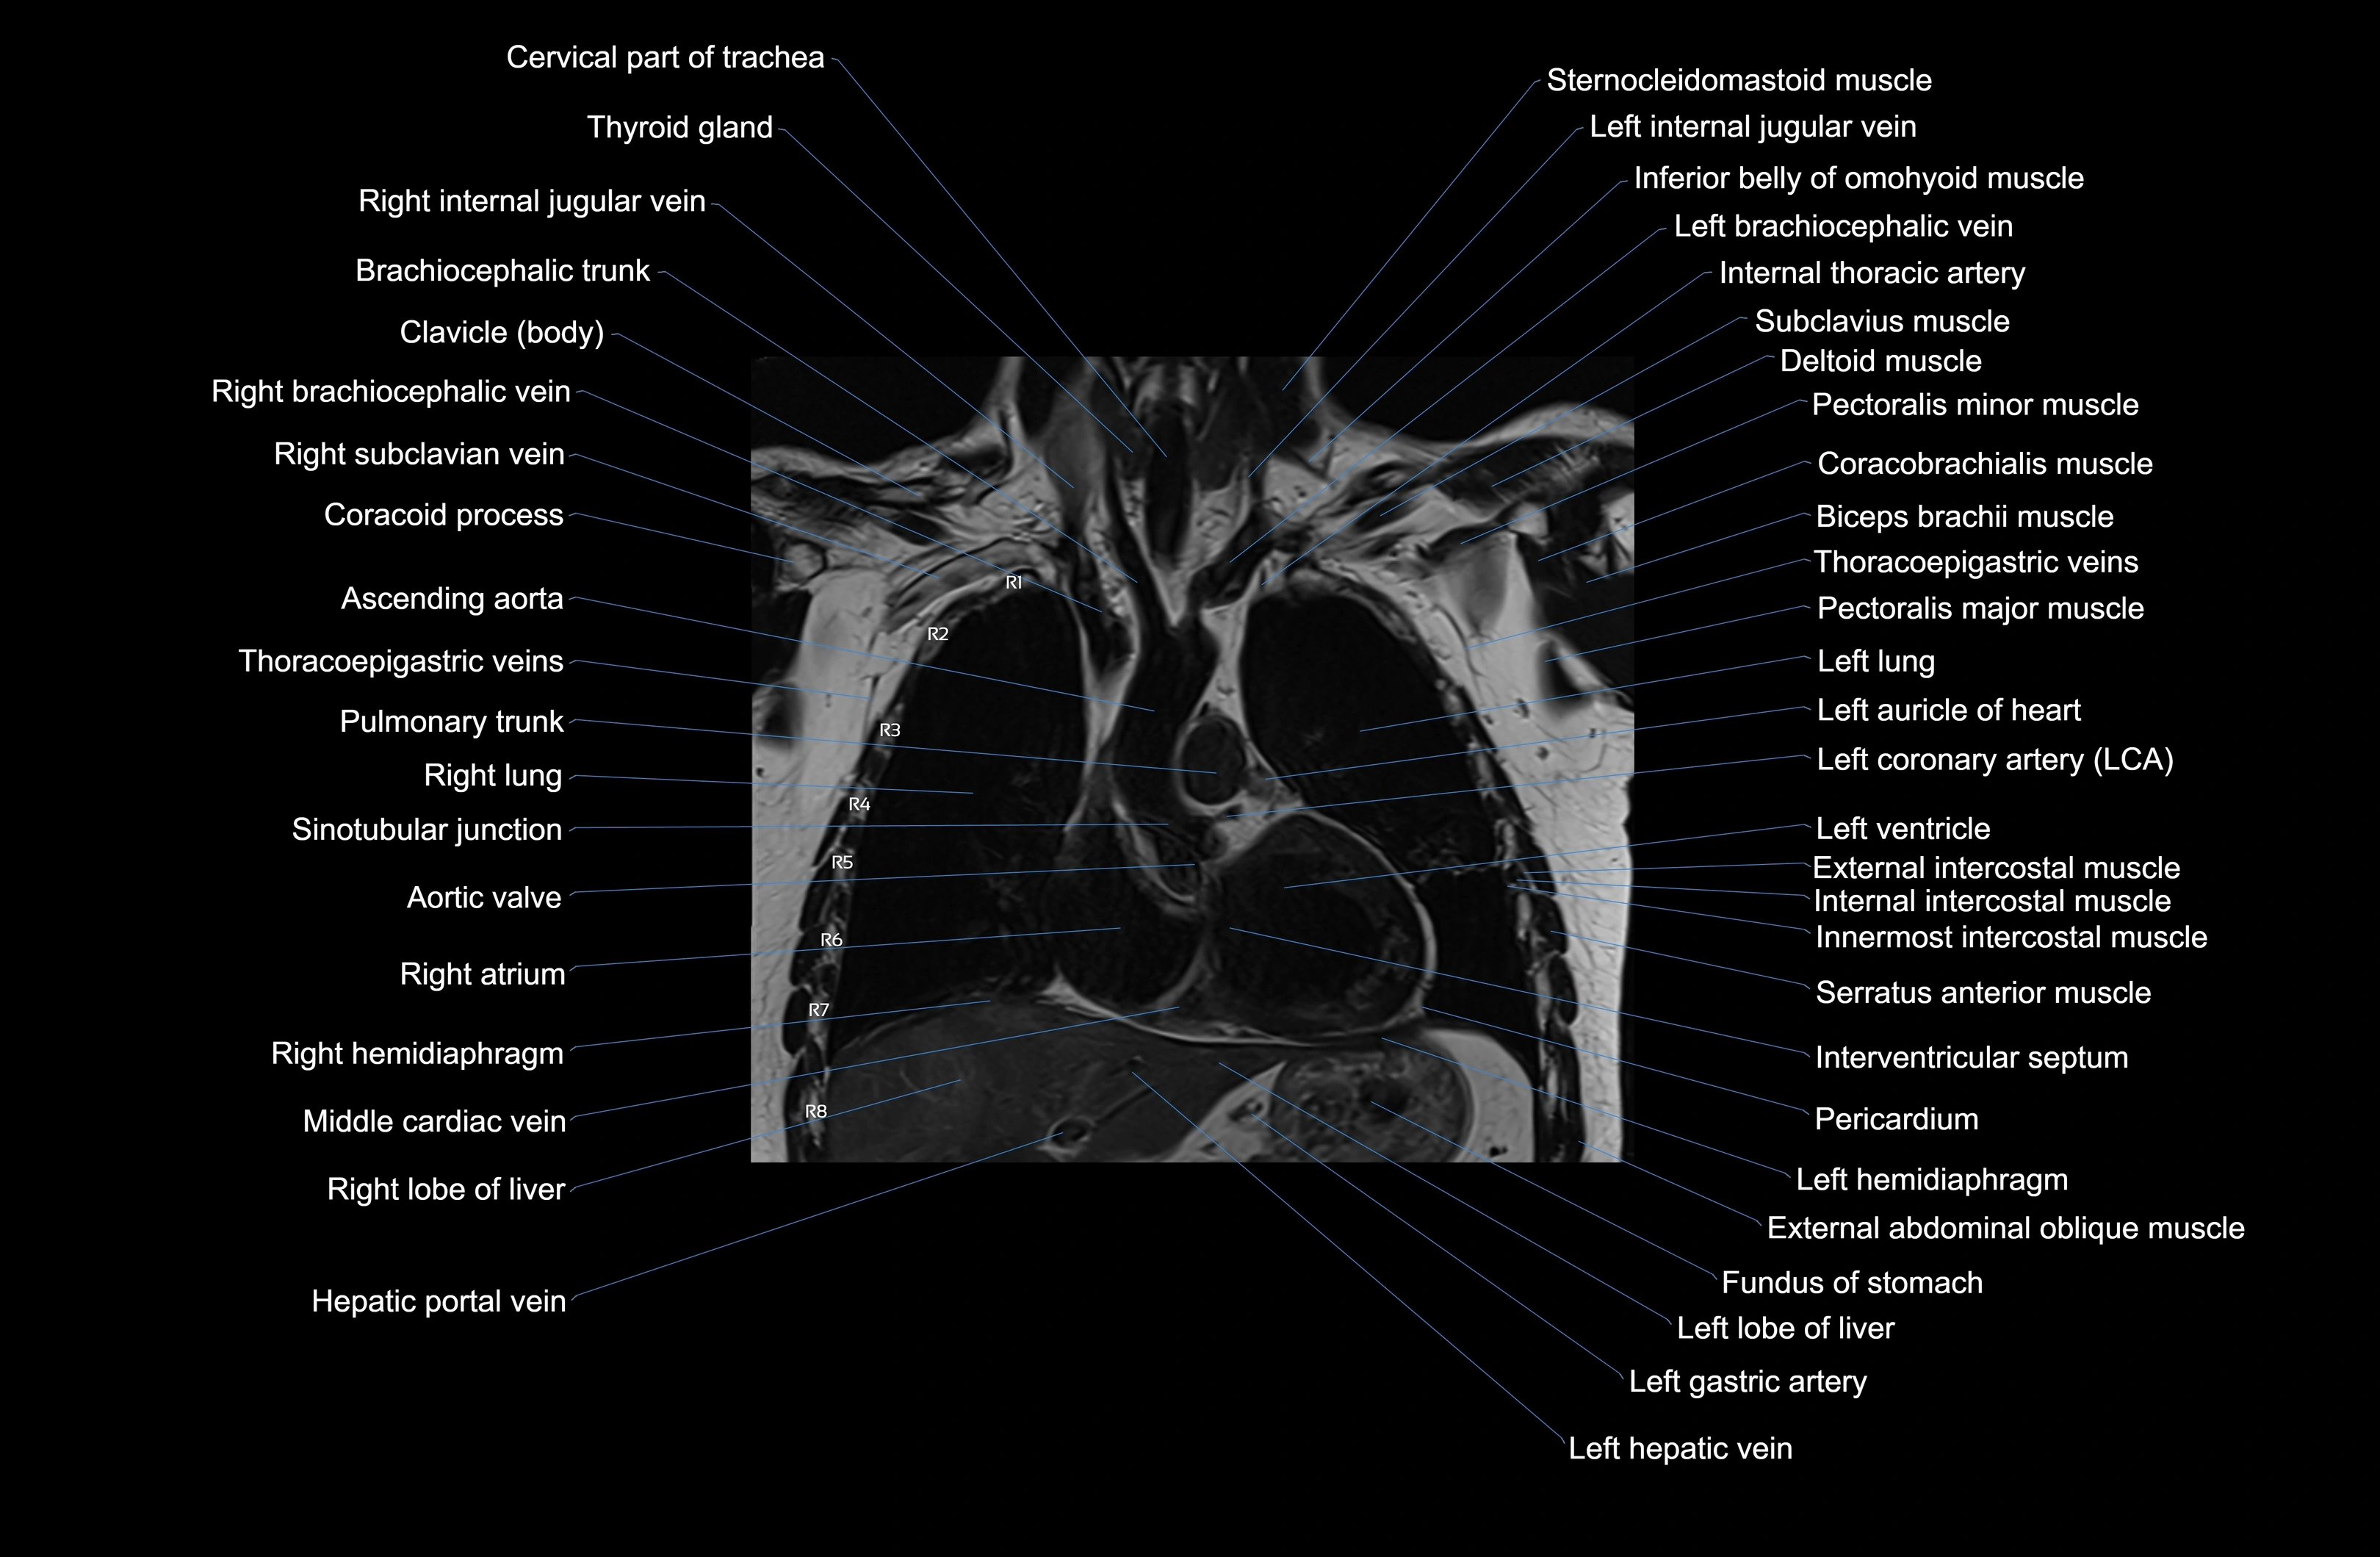

- Ascending aorta

- Brachiocephalic trunk

- Internal thoracic artery

- Left atrium

- Left ventricle

- Pulmonary trunk

- Right atrium

- Right ventricle